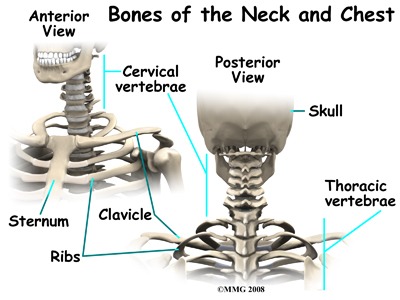

Diagnosis and Medical Evaluation

Diagnosing DHS typically involves a combination of: Neurological assessments, Muscle strength testing, Imaging studies (such as MRI or CT scans), Electromyography (EMG) to evaluate electrical activity in the muscles. Doctors aim to identify whether the cause is primarily muscular or neurological in origin. Ruling out structural issues like herniated discs or spinal injuries is also important during evaluation. In the case of the young man in Iran, medical imaging and clinical tests confirmed a fixed kyphotic posture (forward curvature of the upper spine) without signs of trauma. He also experienced persistent discomfort and sensations in his upper limbs, indicating possible nerve involvement.